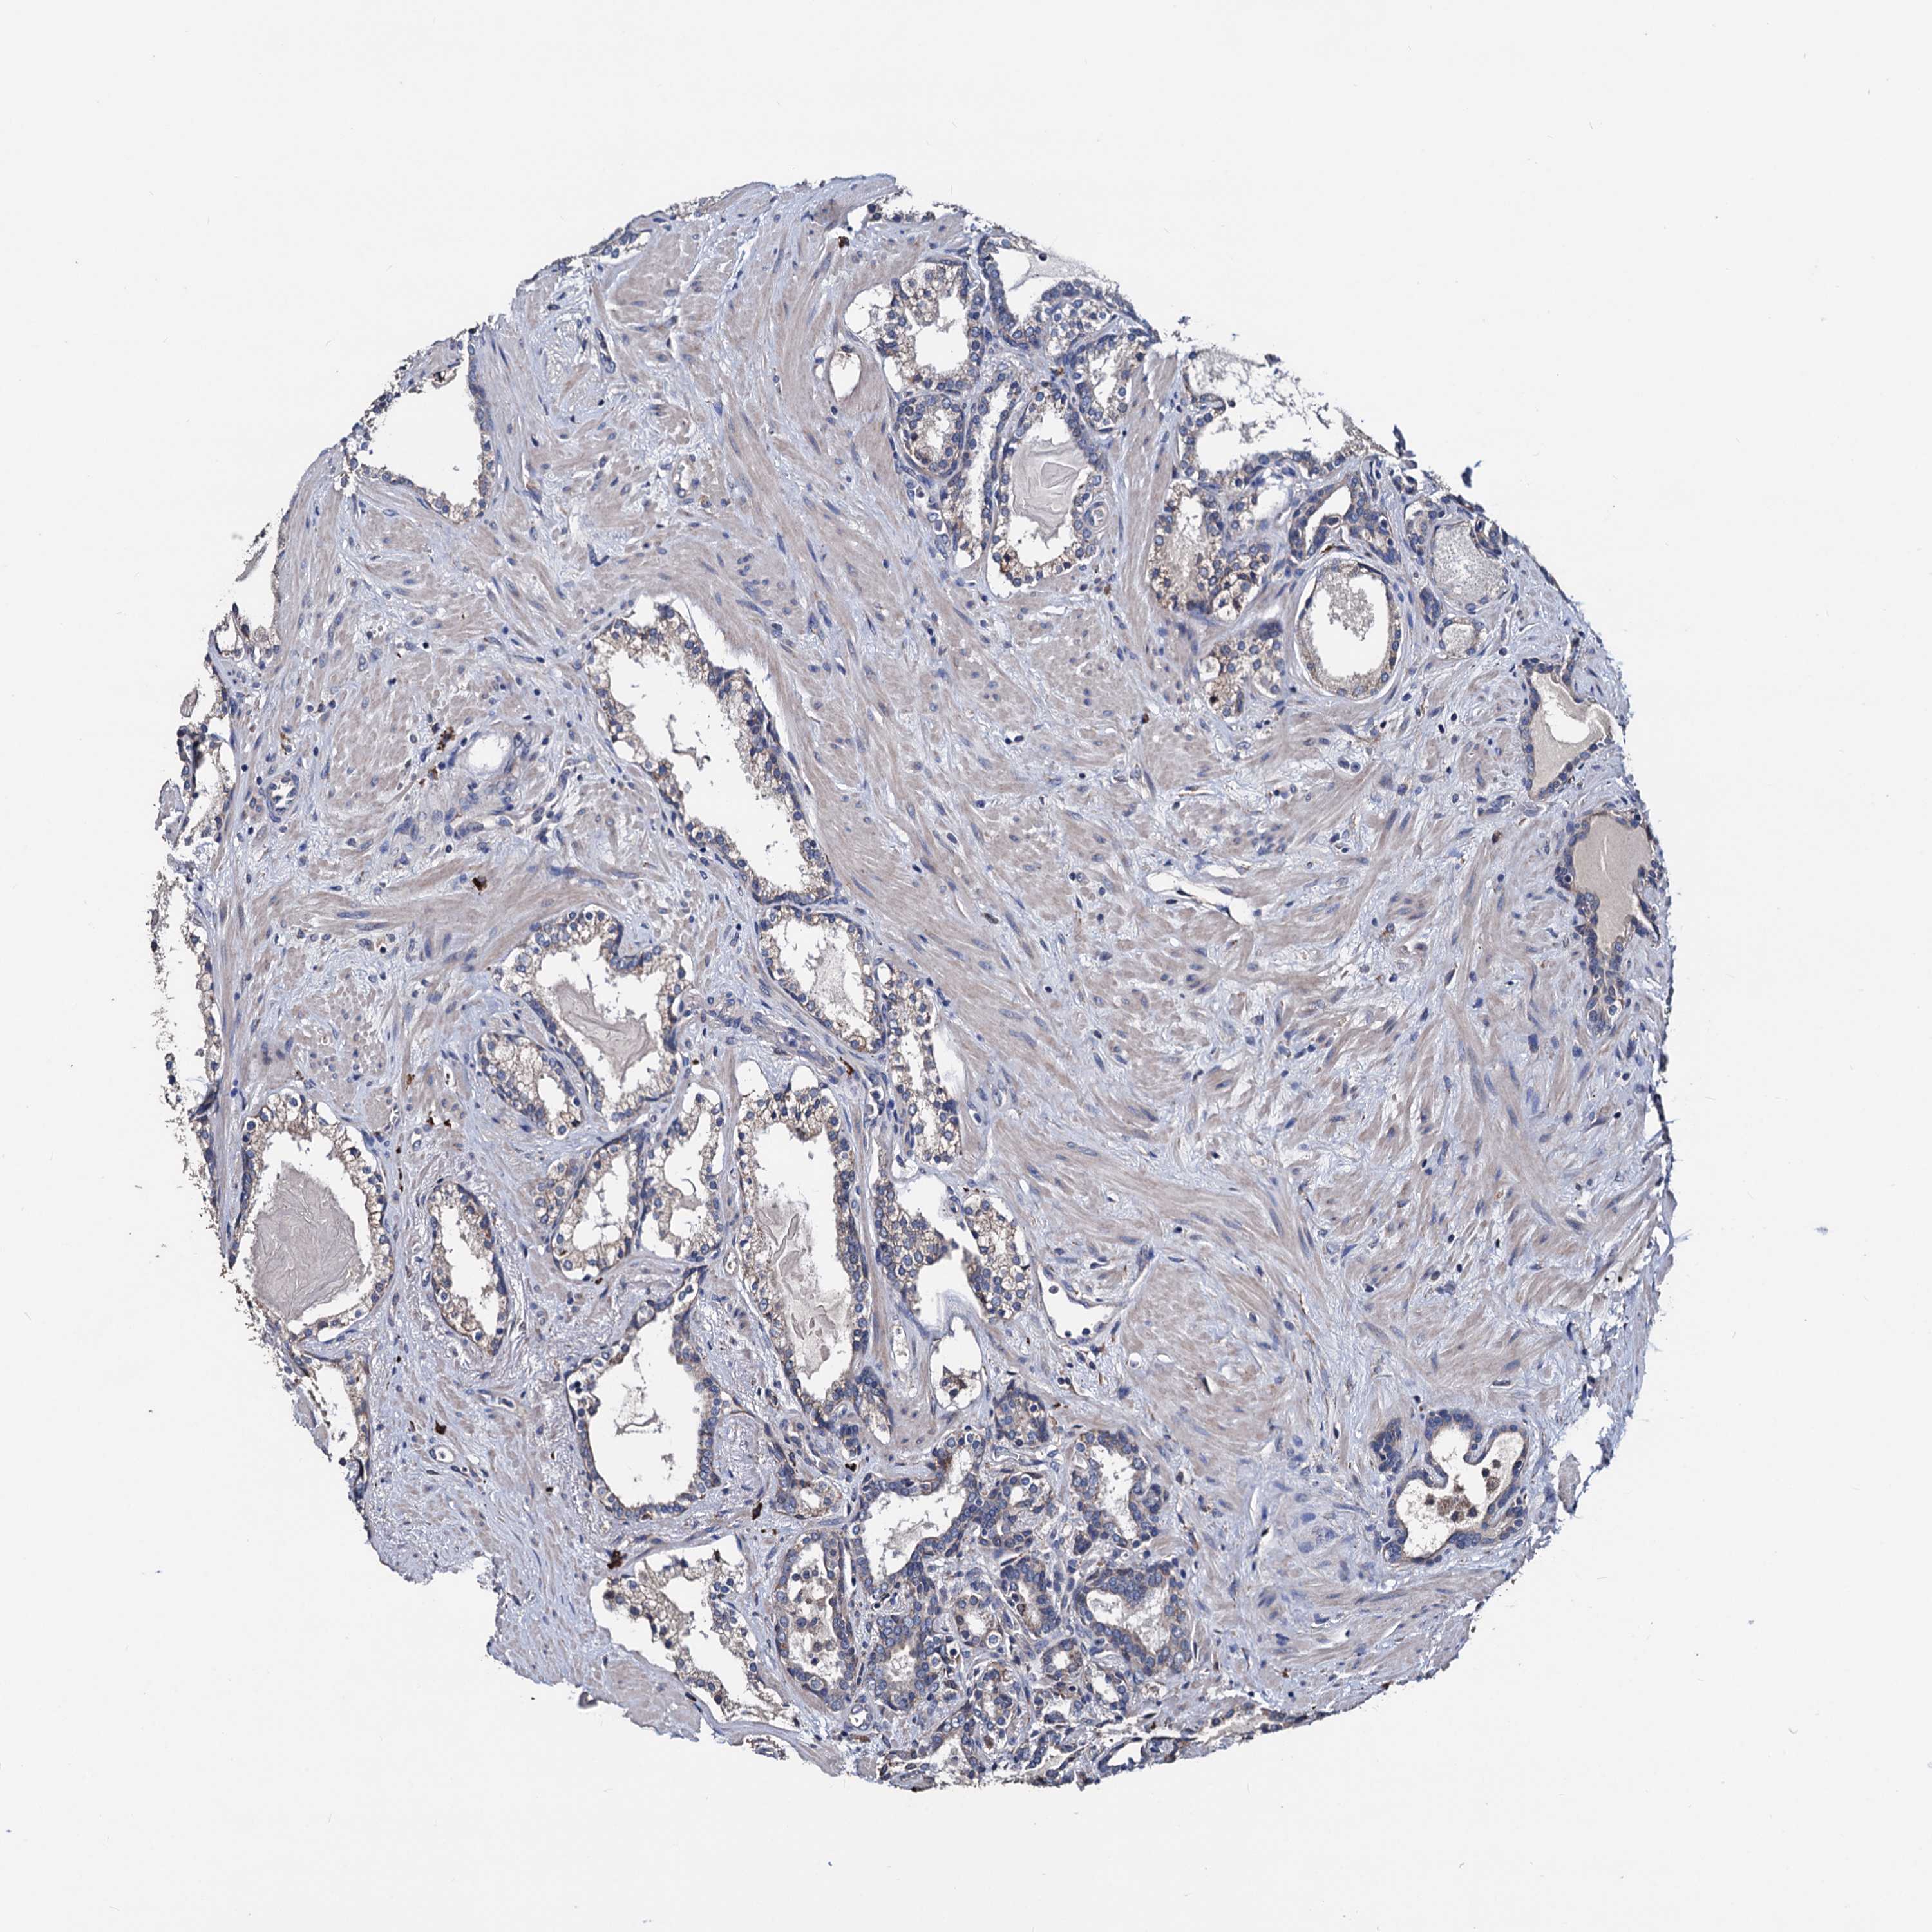

PROSTATE CANCER - Protein expressioni

A mouse-over function shows sample information and annotation data. Click on an image to view it in a full screen mode. Samples can be filtered based on level of antibody staining by selecting one or several of the following categories: high, medium, low and not detected. The assay and annotation is described here.

Antibody stainingi

Antibody staining in the annotated cell types in the current human tissue is reported as not detected, low, medium, or high, based on conventional immunohistochemistry profiling in selected tissues. This score is based on the combination of the staining intensity and fraction of stained cells.

Each image is clickable and will lead to virtual microscopy that enables deeper exploration of all samples and also displays staining intensity scores, fraction scores and subcellular localization as well as patient and tissue information for each sample.

Antibody HPA039089

Staining

High

Medium

Low

Not detected

Intensity

Strong

Moderate

Weak

Negative

Quantity

>75%

75%-25%

<25%

None

Location

Nuclear

Cytoplasmic/membranous

Cytoplasmic/membranous,nuclear

Adenocarcinoma, NOS

Adenocarcinoma, High grade

Adenocarcinoma, Low grade